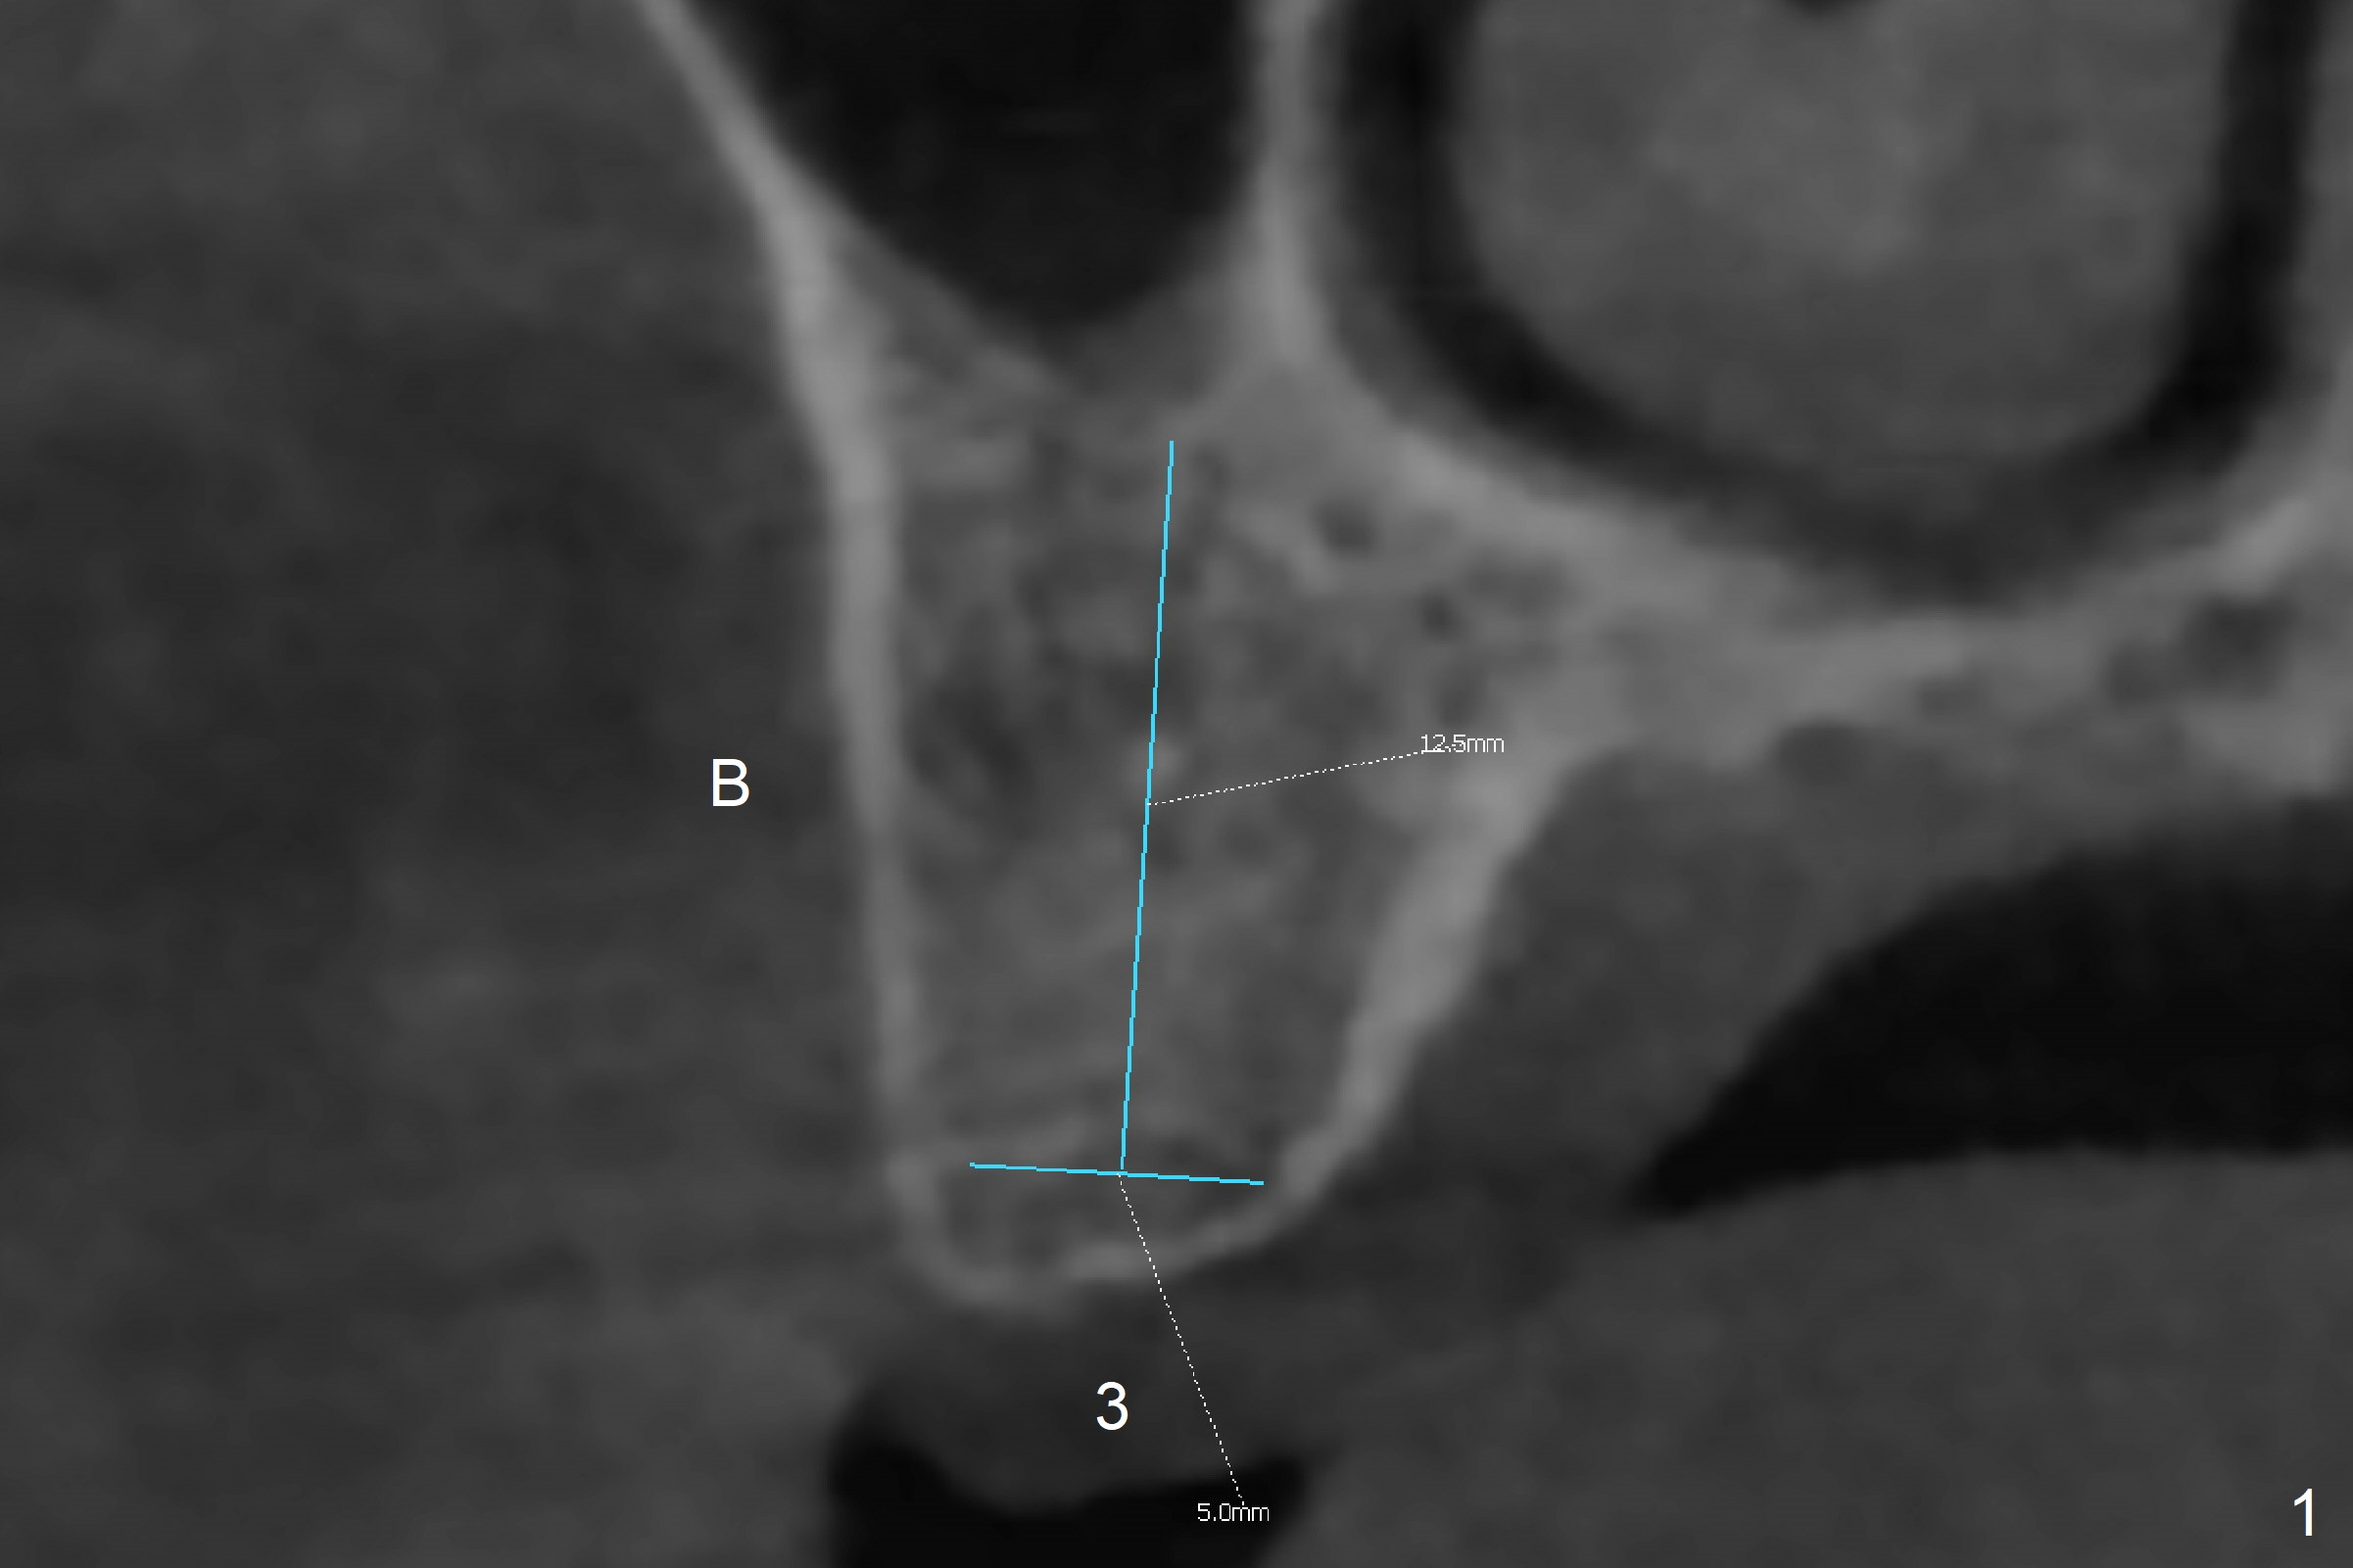

In order to place a 5x11.5 mm implant at #3 completely in depth, the preop CBCT coronal section is reanalyzed (Fig.1). It appears that extra 1 mm osteotomy does not perforate the sinus floor. After finishing osteotomy according to the guide plan, a 3.5x13 mm drill is used ~ .5 mm shy of the depth without sign of sinus membrane leakage. The implant is placed with apparently satisfactory depth, but it is quite close to the curved root tip of the neighboring tooth (Fig.2,3). In fact postop CBCT shows that there is a clearance (Fig.4). To prevent the similar event in the future, the implant should be designed slightly distal. The postop CBCT also shows that the extra depth is not necessary (Fig.4 *); it seems that the inherent 1.2 mm drill tip is sufficient for the depth overprep. The implant is stable for impression 6.5 months postop (Fig.5), whereas that placed immediately free hand is unstable 7.5 months postop. Two weeks later, the patient experiences severe pain when the abutment is being retightened. The crown at #3 is delivered 3 months later (9 months postop). It appears that the bone heals slow in this patient.